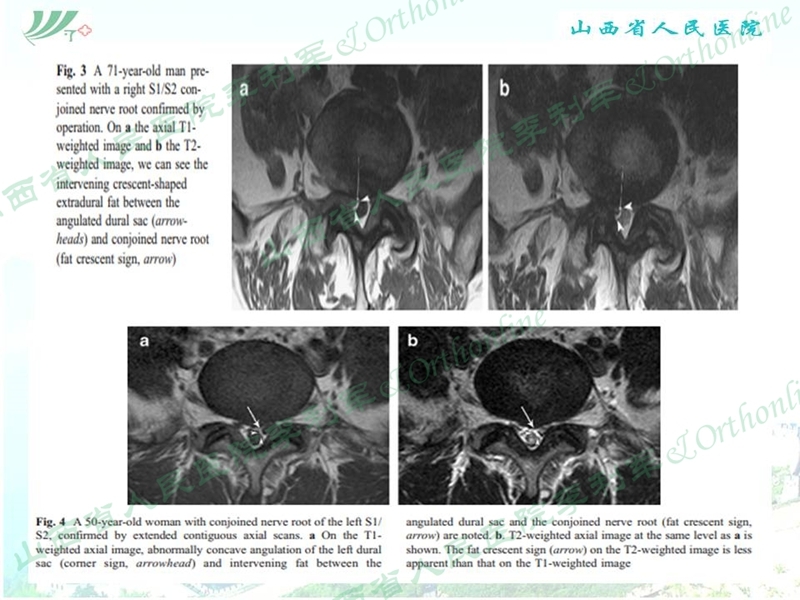

山西省人民医院李利军医生根据自己临床遇到的部分病例,归纳常见的特殊腰椎间盘突出为:高度游离间盘突出,伴有钙化的间盘突出,巨大间盘突出,复发间盘,极外侧间盘突出,易误诊为肿瘤的间盘突出,伴有神经变异的间盘突出等;并根据自己的临床体会对以上特殊类型间盘突出的孔镜治疗作了一些技术总结,以期达到抛砖引玉的作用,并等到大家的批评和指导。